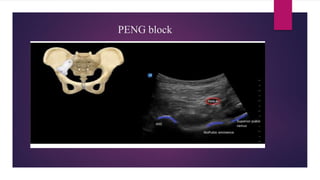

PENG block

• Pericapsular nerve group block - Giron Arango

• Plane block

• Obturator nerve (ON), accessory obturator nerve (AON) and femoral nerve (FN) - major

contribution in innervation of anterior hip capsule

Indication: Preoperative and perioperative analgesia for fracture neck of femur

Possibly can be used for postoperative analgesia following total hip arthroplasty

• Position : Supine with hip extended

• Equipments : Curvilinear transducer

20 ml of local anesthetic (0.25% Bupivacaine/ 0.375% of Ropivacaine)

8 to 10 cm, block needle

Sterile gloves

• Confirmation of side

Avoid : Patient refusal

Allergy/anaphylaxis to LA

Significant coagulopathy